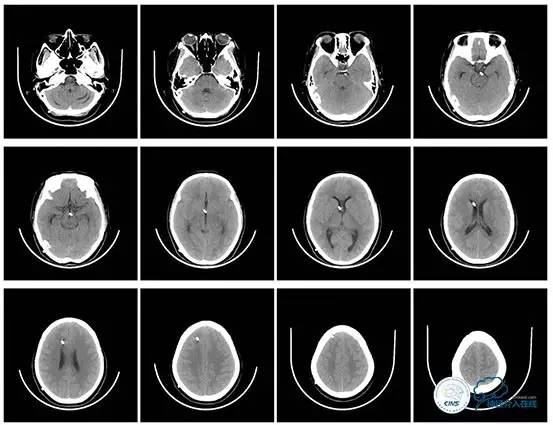

头颅CT

复查头颅及颞骨CT未见明显异常。

头颅CT(2017.6.20)